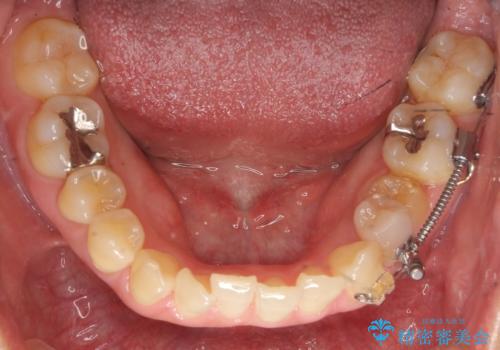

埋まっている奥歯を引っ張り出す インビザライン矯正

- インビザライン および ワイヤーによる部分矯正

- 前歯のがたつきと左下の歯がうまっているとのことで、矯正治療を希望されました。

埋まっている奥歯を並べることで、その後ろの倒れ込んだ歯を整直させることができました。

引っ張り出すことはマウスピース矯正では難しい為、埋まっている歯を並べるスペース確保と、引っ張り出すのに、ワイヤーを用いた部分矯正を行なっています。

上の歯はマウスピース矯正で、奥歯を後ろに下げて、左のかみ合わせのズレを直しています。

上下とも非抜歯で並べています。